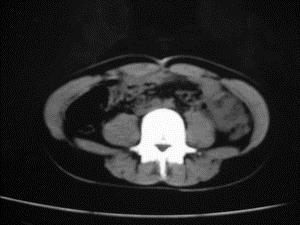

患者女,20岁,被车撞伤3小时,pe:全腹肌紧张,压痛反跳痛,以右上腹为著,肠鸣音减弱。有手术结果。![]() ![]() ![]() ![]() ![]() ![]() ![]() ![]() ![]() ![]() ![]() ![]() ![]() ![]() ![]() ![]() ![]() ![]() ![]() ![]() ![]() jiajie发言: ![]() 考虑空腔脏器穿孔。 dyqct发言:考虑:1、肝左叶外侧段断裂伤伴少量腹血。2、空腔脏器穿孔。 fangzheng发言:仅见腹腔内游离气体,提示空腔脏器穿孔。 guoke发言:胃内密度增高,肠腔内充满气体,考虑肠腔破裂出血 mmg94发言:胃后壁见一增厚软组织密度影,肝左叶前见游离气体影,左腹腔内局部肠管壁、系膜增厚。并见类圆形软组织。以上征象提示消化道管腔破裂,小肠、肠系膜挫裂伤,腹腔血肿形成。 拾荒者发言:肝实质密度不均匀,胃内见不均匀高密度影。考虑:肝挫裂伤,胃内应激性溃疡出血。 守望可可西里发言: 以下是引用jiajie在2006-6-20 15:49:00的发言:[br] [br][br]考虑空腔脏器穿孔。jiajie老师,我鼓起了很大的勇气才决定给您唱个反调儿,如果我错了,请您一定给我指出来,谢谢您了。我反复看了解剖图谱,觉得您所说的“考虑空腔脏器穿孔”上图所用箭头标明的不是游离气体。请您看以下几幅图片: ![]() ![]() ![]() ![]() ![]() ![]() ![]() ![]() 再请您看向医生老师发表的解剖图谱3幅 ![]() ![]() ![]() 这以下几幅图,我认为是肝包膜下积血。不过,说实在话,我没有发现有明显的肝挫裂伤。不对的地方请您一定指出来,再次感谢您了,jiajie 老师! ![]() ![]() ![]() ![]() 这下面几幅图片,我认为有明显的左中上腹部小肠损伤。 ![]() ![]() ![]() ![]() ![]() ![]() ![]() ![]() jiajie 老师,估计我说的是错误的,但我实在闹不明白,请您一定不要笑话我,并指出我的错误,以便于我减少工作中的失误。再次感谢您了,jiajie 老师! 至于胃内的不均匀高密度,我认为拾荒者战友说的有道理,胃内应激性溃疡出血和胃内容物混合所致。 手术结果:左肝叶(iv段)前缘长约8cm挫裂伤口,舌叶根部下< |